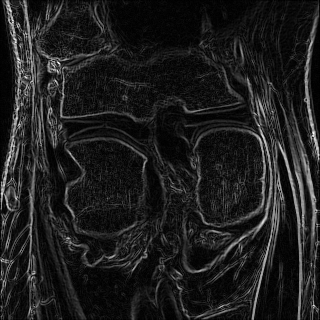

6.2.2 Quality of the Predicted Edges

EPN is utilized to provide edge priors for later reconstruction, so the quality of the predicted edges is very important. In Fig. 10, we provide some qualitative results of the predicted edges of EPN on three multi-coil datasets. Among them, the GT edges are extracted using the Sobel operator. As can be seen from the images, our proposed EPN can predict an approximate contour for the overall subject and can reconstruct accurate edges close to the GT edges under two acceleration factors. This fully verifies the effectiveness and excellence of the proposed EPN.

(a)

(b)

(c)

(d)